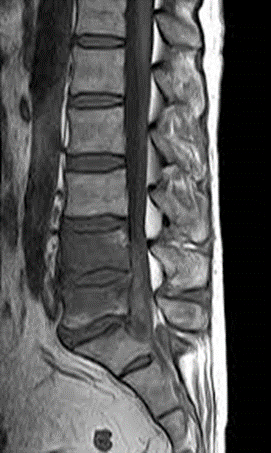

4. Unpasteurized milk / Brucella (spondylitis)